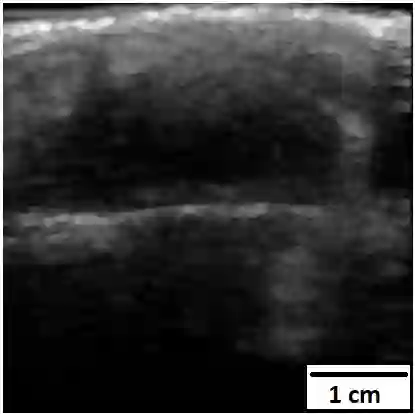

Chronic wounds including diabetic and arterial/venous insufficiency injuries have become a major burden for healthcare systems worldwide. Demographic changes suggest that wound care will play an even bigger role in the coming decades. Predicting and monitoring response to therapy in wound care is currently largely based on visual inspection with little information on the underlying tissue. Thus, there is an urgent unmet need for innovative approaches that facilitate personalized diagnostics and treatments at the point-of-care. It has been recently shown that ultrasound imaging can monitor response to therapy in wound care, but this work required onerous manual image annotations. In this study, we present initial results of a deep learning-based automatic segmentation of cross-sectional wound size in ultrasound images and identify requirements and challenges for future research on this application. Evaluation of the segmentation results underscores the potential of the proposed deep learning approach to complement non-invasive imaging with Dice scores of 0.34 (U-Net, FCN) and 0.27 (ResNet-U-Net) but also highlights the need for improving robustness further. We conclude that deep learning-supported analysis of non-invasive ultrasound images is a promising area of research to automatically extract cross-sectional wound size and depth information with potential value in monitoring response to therapy.